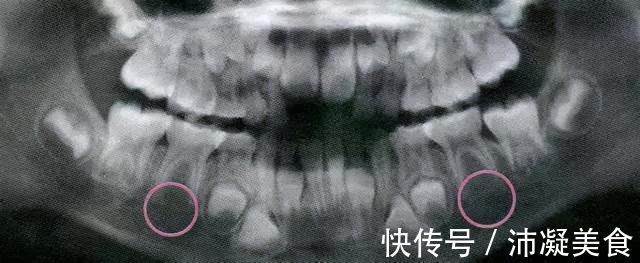

我知道孩子的乳牙掉了的话,会长出永久牙。但是,并不是所有人都遵守这个规则,一定比例的孩子天生就缺恒牙,所以乳牙掉了就长不出牙了。为了判断孩子是否有恒牙,需要X射线检查。如果你的孩子牙齿长时间没有长出来,我建议你尽快带他检查X射线。